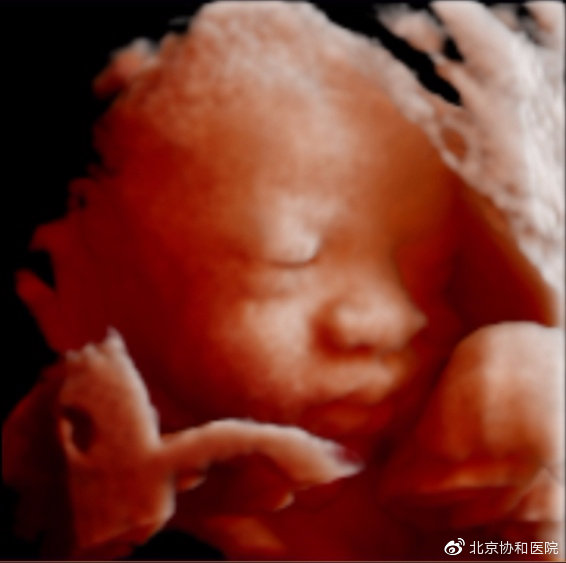

四维超声即实时三维超声,是在二维超声的基础上,通过技术处理而形成的形象直观的动态立体图像,除了对胎儿头面部、四肢的立体呈现,还能更细致地观察到心脏、肝脏等全部内脏器官。在病变较小、诊断疑难时,借助四维超声得到的更优图像,能够提高诊断准确率。